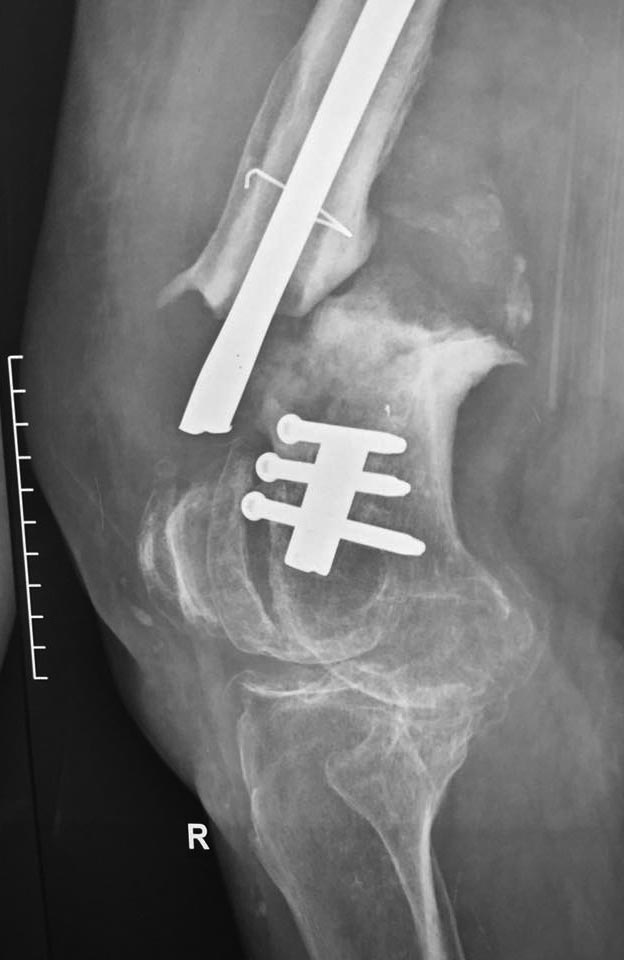

Пациентка 72 года поступила в клинику с диагнозом несросшийся в условиях остеосинтеза перелом н/3 правой бедренной кости, перелом фиксатора ( в анамнезе 3 неудачные операции на бедре по поводу вышеуказанного диагноза). Интересует Ваше мнение по поводу тактики лечения пациентки.